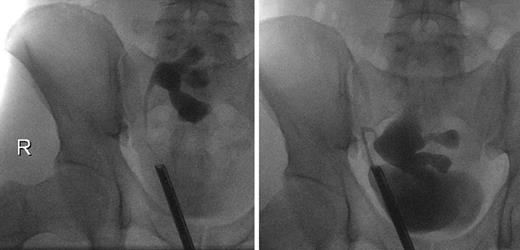

On the 51st postoperative day, the patient presented an elevated creatinine of 241 μmol/L and a stable hydronephrosis, so that a stent insertion was necessary. The retrograde ureteropyelography showed no pathologies (Fig. 2), and the creatinine levels decreased afterwards. The perfusion of the kidney was adequate. The removal of the ureteral stent was successfully performed 3.5 months later. In the 9th postoperative month, a scintigraphy was performed and showed a functional obstruction of the kidney transplant, so that we initially refrained from further interventions.

The following ultrasound controls showed a progredient hydronephrosis, requiring a reinsertion of the ureteral stent. Furthermore, the patient reported a hypermobility of the transplant in his pelvis. The intraoperative ureteropyelography confirmed this by showing a hypermobility of the kidney depending on the degree of bladder filling (Fig. 2). According to this diagnosis, a robot-assisted transplant nephropexy was performed. Further sonographic controls showed a stable pelvic ectasia with stable creatinine levels around 111 μmol/L.